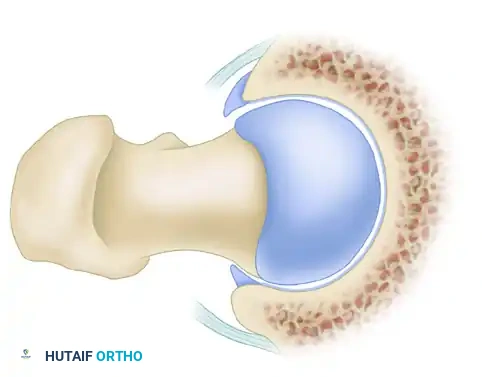

Cam impingement is predominantly observed in young, active male patients. It is characterized by an abnormally shaped, nonspherical femoral head with a decreased head-neck offset. This aspherical extension of the epiphysis (often referred to as a "pistol grip" deformity) creates a cam effect as the femoral head rotates into the acetabulum.

During dynamic hip flexion and internal rotation, the prominent cam lesion forcefully abuts the anterosuperior acetabular rim. Because the cam lesion is larger than the corresponding acetabular opening, it acts as a wedge, generating massive shear forces across the articular surface.

Over time, this repetitive shearing leads to delamination of the acetabular cartilage from the subchondral bone and subsequent avulsion or detachment of the labrum from the articular margin. The labrum itself is often pushed outward, resulting in an "outside-in" pattern of failure.